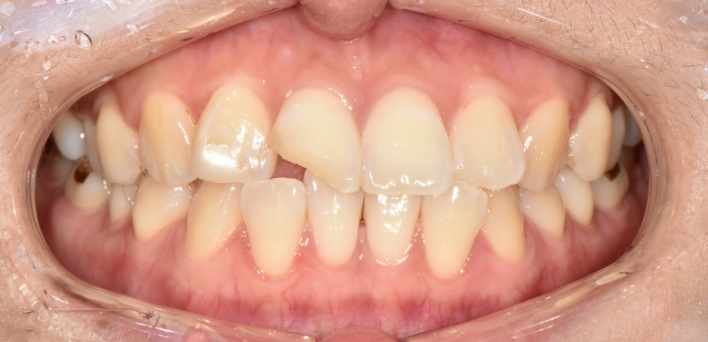

우리 얼굴에서 미소는 첫인상을 좌우합니다. 이런 좋은 인상을 위해 라미네이트를 고려 중이시라면,

많은 것들을 고려해야 합니다. 라미네이트 시 무조건 하얗고, 얇기만 한 치아가 좋은 것은 아닙니다.

개개인의 얼굴마다 비율에 맞게 이상적인 치아의 형태가 있습니다.

※ 더서울치과의원은 의료법을 준수하며 위 케이스는 실제 환자의 동의를 얻은 사례로 치료 전, 후가 동일한 환경에서 촬영되었습니다.

환자 케이스에 따라 부작용이 발생할 수 있습니다. 이 부분은 의료진의 충분한 상담과 체크를 통해 예방하고 줄일 수 있습니다.

[심미치료 부작용] 시술 후 치아 시림, 보철물 파손 등의 부작용이 발생할 수 있어 개인별 치아 상태에 따른 정확한 진단과 사후 관리가 중요합니다.